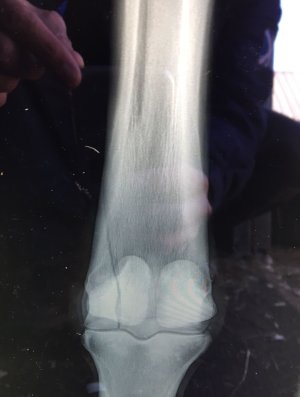

From a other thread I realised I have so many funky images on by phone of various xrays and tendon scans etc. So the ones with no names visible I will pop up here one at a time for you to figure out what's wrong.

We will start off with an easy one - tell me what you think the problem is and then give me the solution:

2 screws. And no fancy smancy hi tech kit either - a DeWalt drill, some major heavy duty screws from screwfix and some saline. A few months rest then back into training. The horse ran for a few more years and won a couple as well after this.